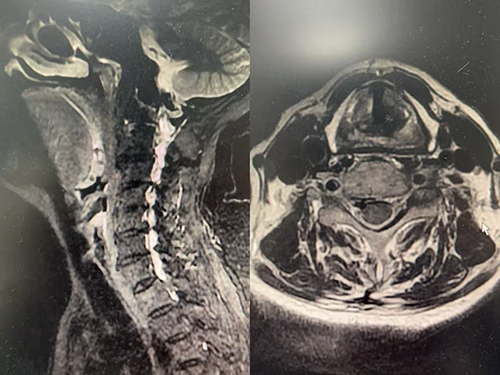

(术前颈椎影像)

据胡蓉副主任介绍,患者王嗲嗲受颈椎病的折磨三年余,右侧颈椎肩膀腋窝疼痛难忍,右手麻木不适,夜不能寐,吃饭也不香。已经在诊所和多个医院行理疗、吃药、针灸等不见好转。2月14日,患者慕名来到湘雅三医院疼痛科就诊,韩睿副教授门诊接诊后随即为患者办理住院。入院后,医生团队考虑到王嗲年龄较大,COPD合并心功能不全,不能耐受传统开放手术,科室副主任胡蓉医师组织科室医护人员行详细的术前讨论,最后选择在静脉麻醉(鼻咽通气道辅助通气)下为其行经皮穿刺颈椎间盘激光修复术。术中在超声和C臂联合引导下,经皮细针穿刺进入C5/6责任椎间盘,利用970nm波长低能量激光进行椎间盘的汽化和修复,并促进软骨化生,最终达到椎间盘减压和镇痛的目的。该手术方式为微创,伤口仅为一个针眼,出血量极少。